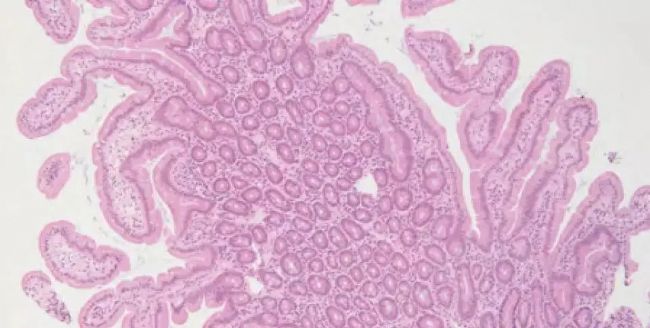

病理诊断的常见手段:病理切片染色

十九世纪显微镜的发明,更是使得人们可以从局部组织的特征对疾病进行诊断分类,这也是现代病理诊断产生的技术基础。随着显微镜的诞生,人们得以对人体组织器官进行细致入微的研究,并形成了科学的现代病理学知识体系。

二十一世纪随着分子生物学赋能临床医学研究,病理的范畴涵盖了从组织到细胞、微生物,再到单个分子及其相互作用,也就相应地形成了组织、细胞、微生物以及分子病理诊断技术。